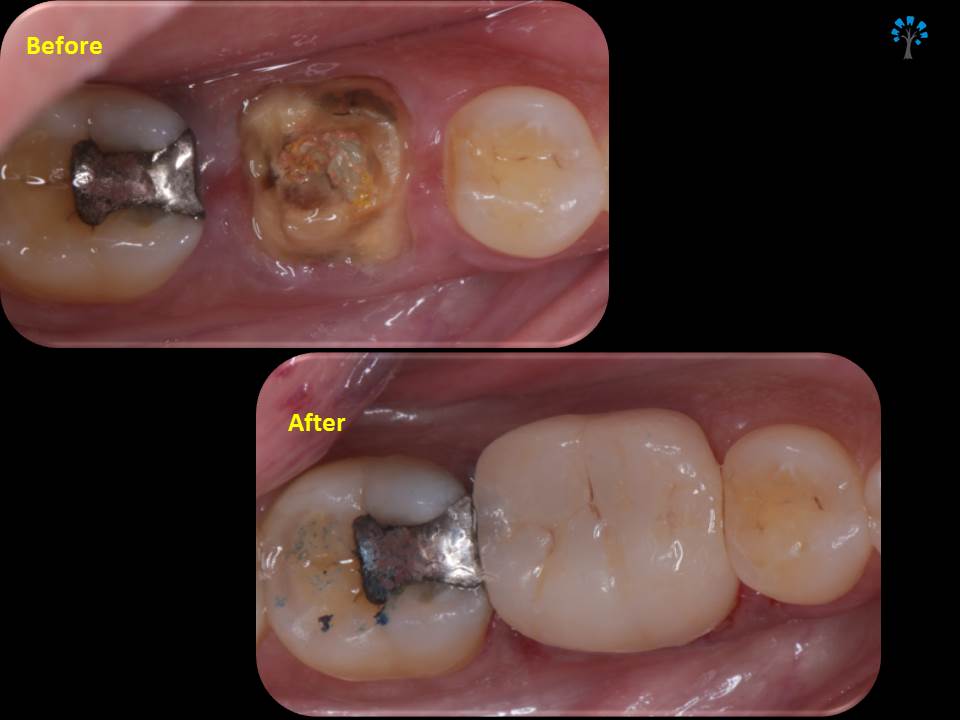

An elderly patient reported with a dislodged gold crown.

Examination revealed fracture of the distal portion of the tooth (Fig 1,4).

Monolithic EMAX crown was fabricated (KATARA DENTAL, PUNE) and bonded.(Fig 10 -12)

Preserving the natural teeth has unique benefits. And by using a bonded restoration we can add years to the life of the tooth.